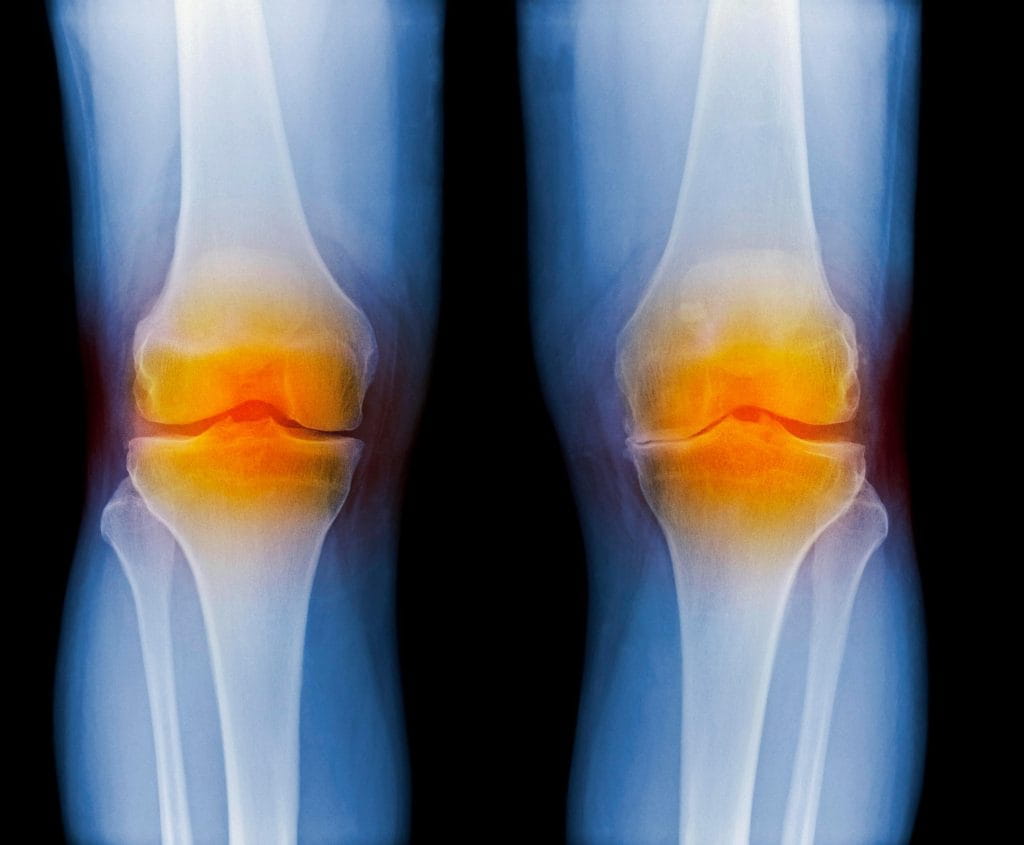

Медицинские состояния: Септический артрит коленного сустава